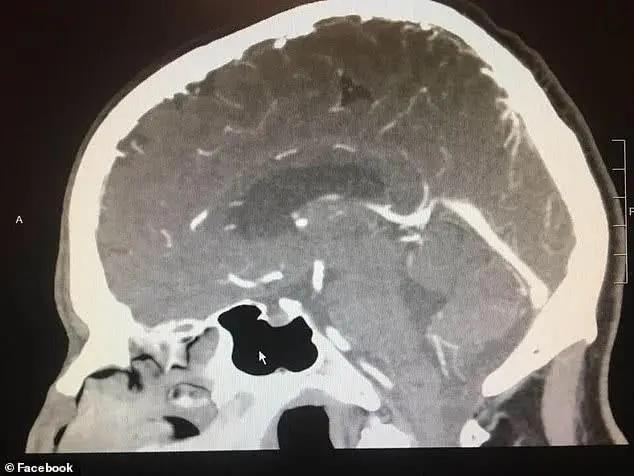

几个月前,伍德先生时常头痛欲裂,病发时不得不扶着墙壁走路。于是,他去医院做了检查。医生们给出了不同的诊断结果:一名加州大学旧金山分校的神经外科医生认为他患有颅内出血;另一名放射科医生认为他脑部有肿瘤。

然而,就在做手术的前一天,伍德先生被告知手术取消了。其原因是:术前的X光片显示,他的脑部已无任何异常。